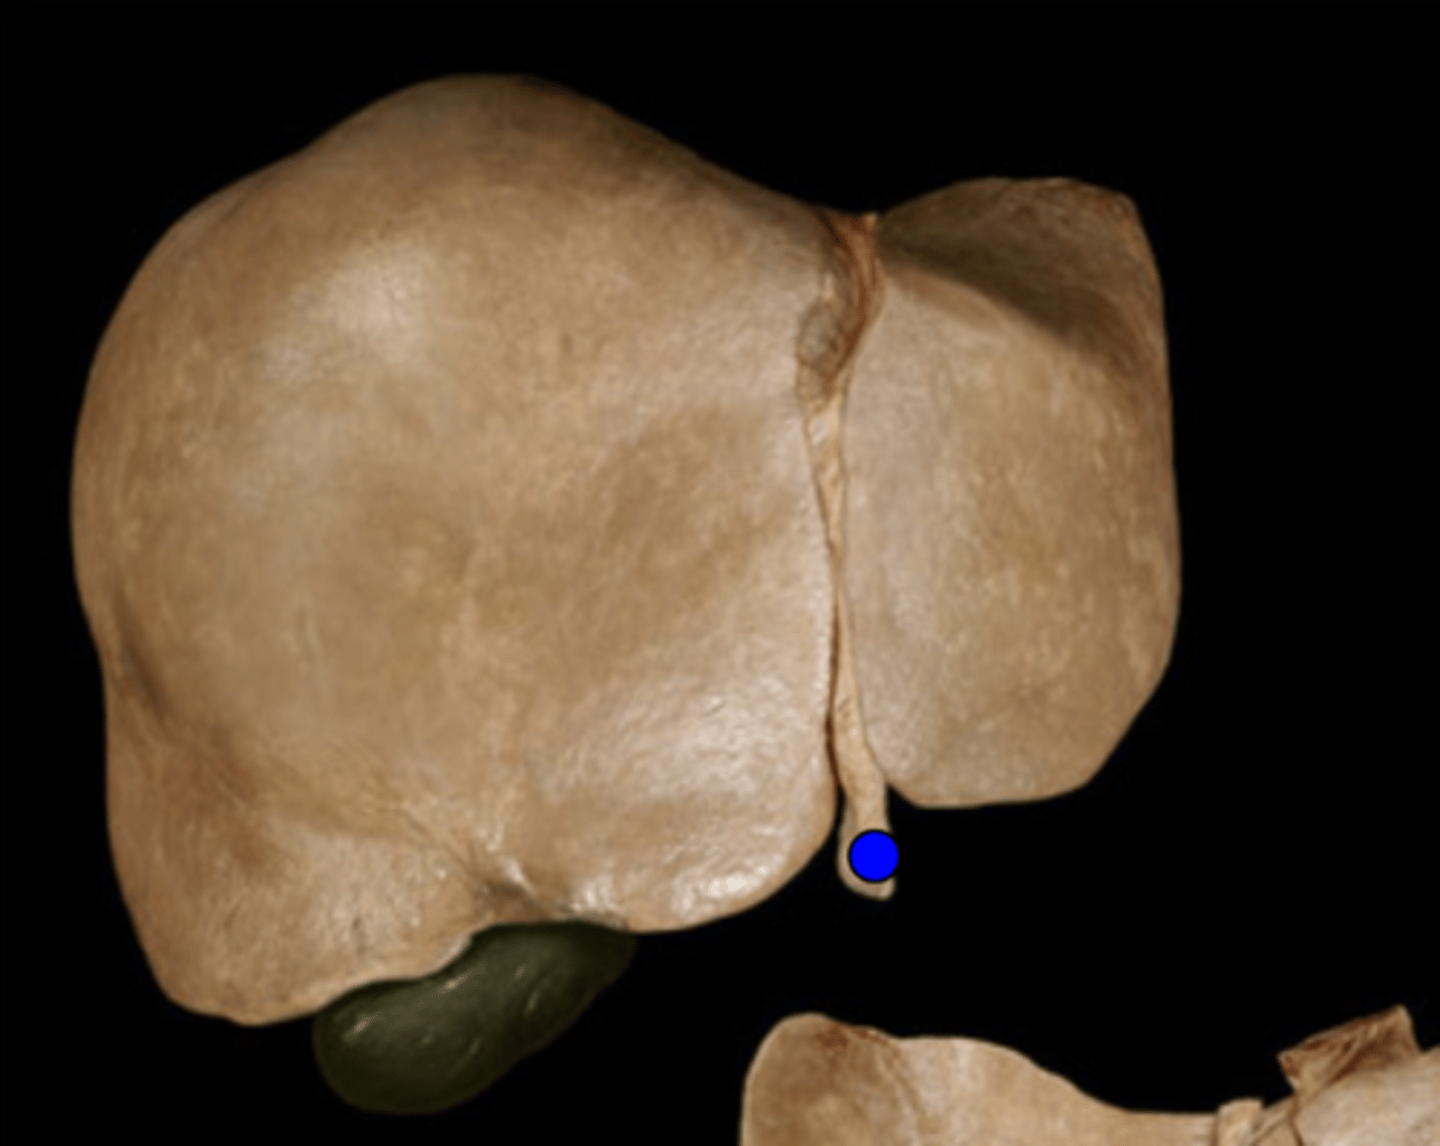

Falciform Ligament

Ligamentum Teres

Gall Bladder